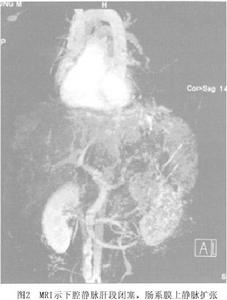

4.血管造影血管造影是明確BCS病變部位的最重要方法。一般可通過以下3種方法了解肝靜脈及下腔靜脈形態和血流動力學變化(圖3,4,5)。

(1)經股靜脈下腔靜脈插管:下腔靜脈完全性梗阻時,導管不能進入正常距離,向上逐漸出現阻抗測壓見下腔靜脈壓顯著升高;如果有下腔靜脈阻塞時,需同時經頸靜脈上腔靜脈插管作雙向造影可清晰顯示膜性結構的形態和阻塞距離的長短。此時,在阻塞部位以下可見附壁血栓,更可清晰顯示迂曲、擴張的腰靜脈、腰升靜脈脊柱前靜脈、膈靜脈及心包膈靜脈,亦可見血流經奇靜脈。可見一支或二支肝靜脈阻塞,阻塞下段擴張,或一支阻塞、另一支代償性擴張,亦可見各支肝靜脈間的分流。若沒有下腔靜脈阻塞操作嫻熟者導管不能進入靜脈,提示肝靜脈有梗阻。